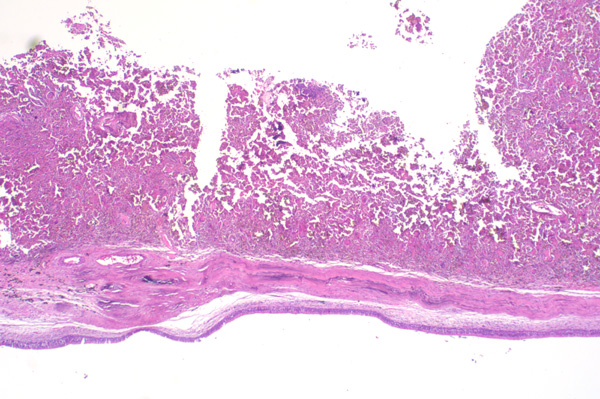

2x   |   Hematoxylin and Eosin

Inflammation extends to the submucosal connective tissue.